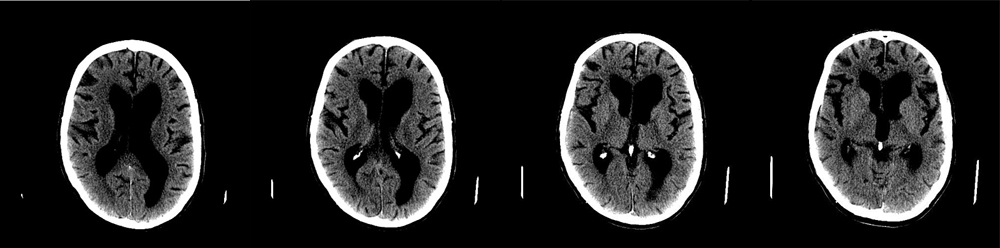

Obstructive Hydrocephalus / Aqueductal stenosis

Case 1 :

54 year old female with delayed milestones, S/P occipital decompression of Chiari malformation, with progressive gait ataxia, adduction paresis of eyes, nystagmus and dementia.

Imaging findings:

Figure 1. Pre-contrast axial CT head

- CT scans without contrast show enlargement of lateral and third ventricles, but not the fourth ventricle, due to aqueductal stenosis.

- The posterior fossa is distorted due to a congenital Chiari malformation and previous surgery.

- Sulci and gyri are flattened against skull and are effaced.